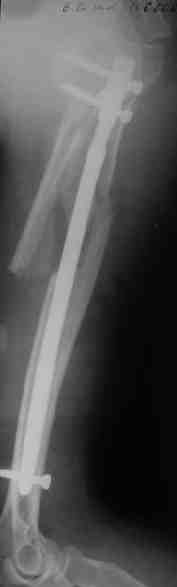

Прооперировали больную с переломом плеча все же гвоздем, Фото в приложении.

Гвоздик похоже ЦИТОвский?

Полагаю, бабушку можно поздравить с обретением

независимости. Судя по снимкам, неврологических расстройств нет и такая пациентка выпишется после снятия швов.

Только сформировали канал в головке. Диафиз не рассверливали. Хотя при необходимости, конечно, рассверлили бы.

Гвоздь большеберцовый нашей модификации, действительно, их делает предпричятие "ЦИТО". Тут взят 9 мм, укорочен до 240 мм, сделано дополнительное отверстие самое проксимальное, ну и для дистального винта.